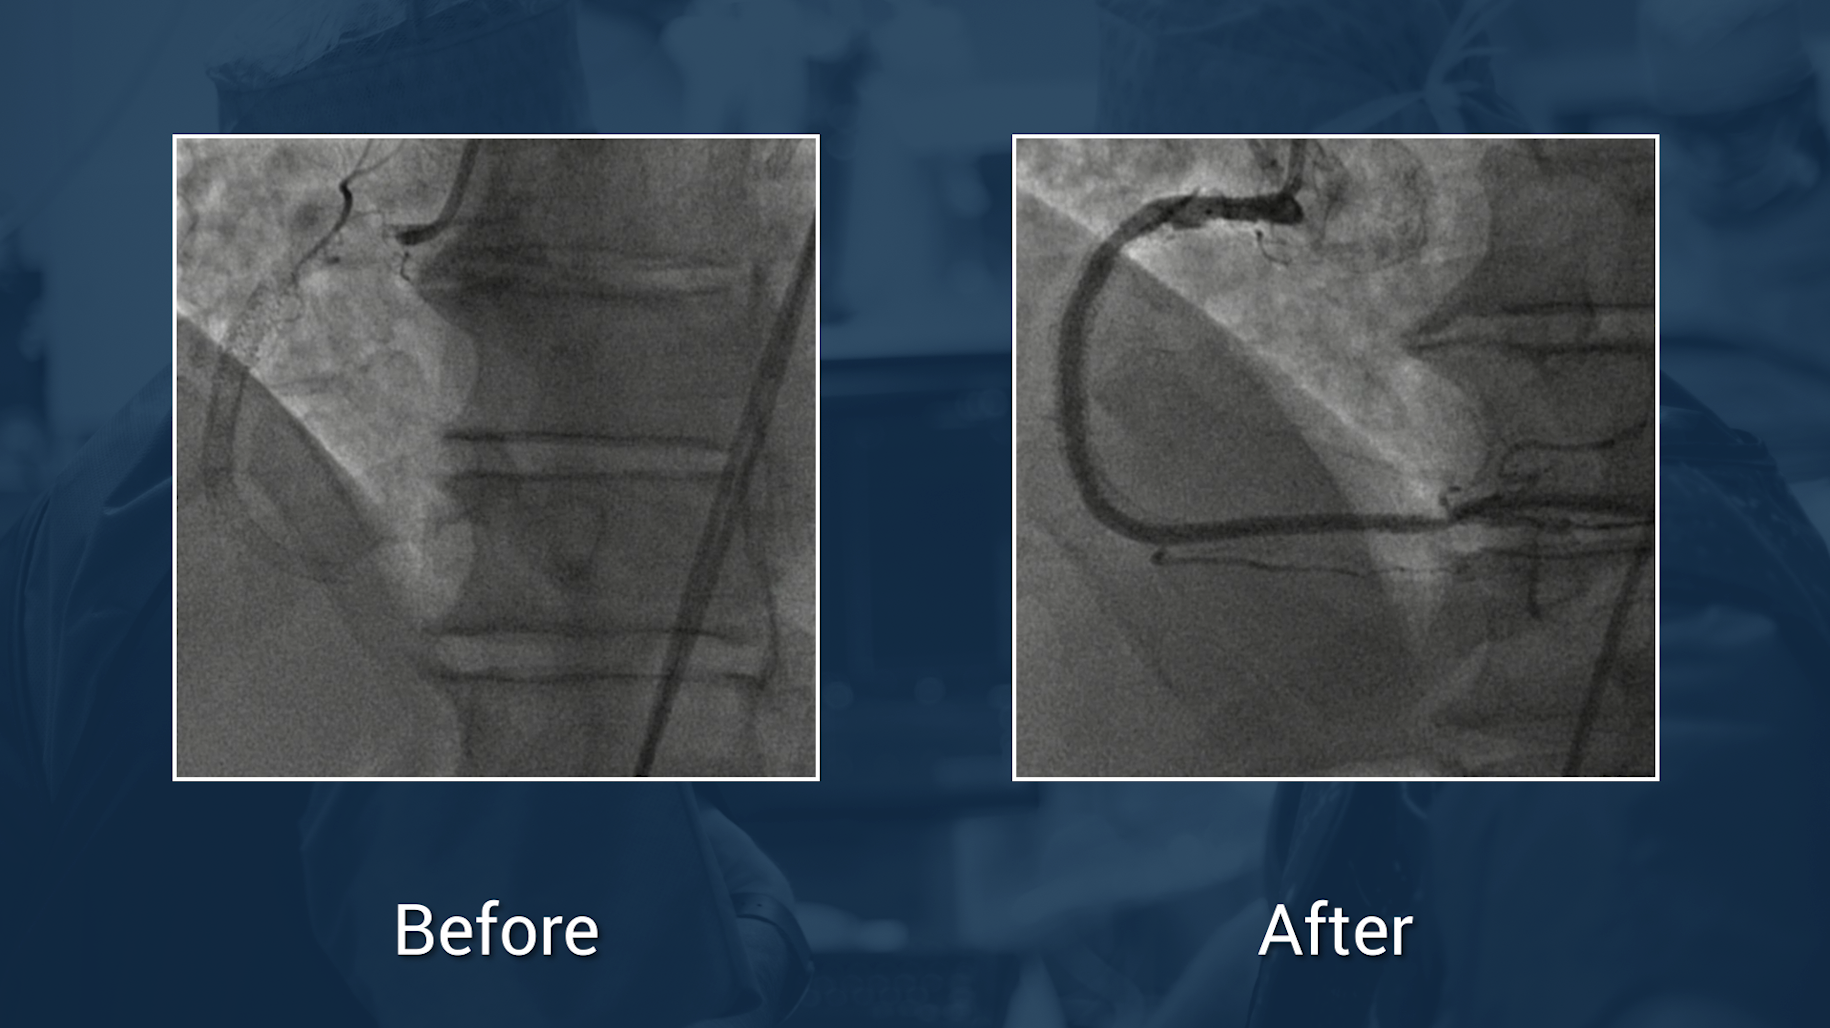

Resténose intrastent AFS gauche traitée par Jetstream* + DCB Ranger*

Dr Jérôme Brunet

Endovascular

Lower limbs

Fempop

Case in the box

Rotational atherectomy for ostial and calcified-SFA lesion under IVUS guidance

See clearly. Treat optimally.

Treatment of heavily calcified popliteal artery with Rotational Atherectomy System and DCB